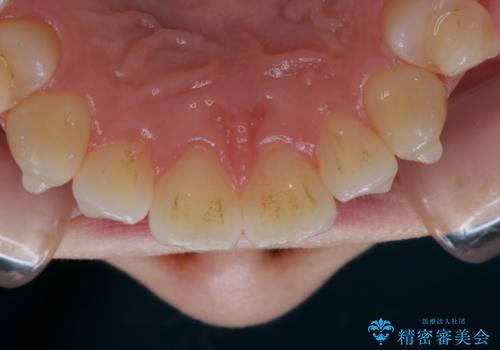

アタッチメント周囲のステインOFFをPMTC で

- インビザライン矯正治療中に、アタッチメント周囲のステインが気になるとのことでした。PMTC30分コースを行いました。

マウスピース矯正インビザライン治療では、歯の表面にアタッチメントという突起を設定します。(アタッチメントは歯の動きを効率的に移動するためのものです)

アタッチメントが歯に付くと、表面が凸凹し磨き残しが多くなったりと、プラークや歯石・着色がつきやすくなることがあります。

矯正治療中もPMTCを定期的に行い、専門的な機械でしっかりと汚れを除去することがおススメです。